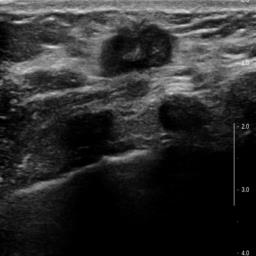

Ultrasonography is an important routine examination for breast cancer diagnosis, due to its non-invasive, radiation-free and low-cost properties. However, it is still not the first-line screening test for breast cancer due to its inherent limitations. It would be a tremendous success if we can precisely diagnose breast cancer by breast ultrasound images (BUS). Many learning-based computer-aided diagnostic methods have been proposed to achieve breast cancer diagnosis/lesion classification. However, most of them require a pre-define ROI and then classify the lesion inside the ROI. Conventional classification backbones, such as VGG16 and ResNet50, can achieve promising classification results with no ROI requirement. But these models lack interpretability, thus restricting their use in clinical practice. In this study, we propose a novel ROI-free model for breast cancer diagnosis in ultrasound images with interpretable feature representations. We leverage the anatomical prior knowledge that malignant and benign tumors have different spatial relationships between different tissue layers, and propose a HoVer-Transformer to formulate this prior knowledge. The proposed HoVer-Trans block extracts the inter- and intra-layer spatial information horizontally and vertically. We conduct and release an open dataset GDPH&GYFYY for breast cancer diagnosis in BUS. The proposed model is evaluated in three datasets by comparing with four CNN-based models and two vision transformer models via a five-fold cross validation. It achieves state-of-the-art classification performance with the best model interpretability.

翻译:超声波分析是乳腺癌诊断的一个重要常规检查,原因是其非侵入性、无辐射和低成本的特性。然而,由于其内在局限性,它仍不是乳腺癌的第一线筛选测试。如果我们能够精确地通过乳房超声图像诊断乳腺癌(BUS),它将是一个巨大的成功。我们提出了许多基于学习的计算机辅助诊断方法,以实现乳腺癌诊断/感官分类。然而,其中多数方法需要事先确定性能模型,然后对ROI内部的跨值进行分类。常规分类支柱,如VGG16和ResNet50等,可以在没有ROI要求的情况下实现有希望的分类结果。但是这些模型缺乏可解释性,从而限制了其在临床实践中的使用。在本研究中,我们提出了一个新的无乳腺癌诊断模型,在超声波图像中进行解释性特征描述。我们利用了先前的解剖学学学知识,即恶性肿瘤和良性肿瘤模型在不同组织层之间有着不同的空间关系,并提议采用状态解析法来编制这一先前的知识。拟议中的HOVer-Trans-Trading-Tradef-trainal Ex-deal-dealal-deal-deal-deal-degraphal-deal-deal-deal-deal-deal-deal disal disal-dal-dal-dal-dal-dal-deal-deal-dal-deal-deal-deal-dal-dal-dal-dal-dal-dal-dal-dal-dal-dal-dal-dal-dal-dal-I-dal-Iversal-dal-Ial-d-d-I-d-d-I-I-I-I-I-I-I-I-I-I-I-I-I-I-I-I-I-I-I-I-I-I-I-I-I-Ial-I-Ial-Ial-I-I-I-I-I-I-I-I-I-I-I-I-I-I-I-I-I-I-I-I-I-I-I-I-I-I-I-I-I-I-I-I-